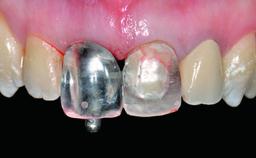

Replacement of a Perforated Upper Left Central Incisor: Early Placement of an RC Bone Level Implant

A 28-year-old patient presented at her general dentist’s office and complained about the appearance of her tooth 21. The patient had a history of trauma to this tooth. Endodontic treatment had been performed in the past and a crown placed on the tooth. A procedure to replace the old crown was performed by her dentist; however, a perforation on the middle third of the root occurred, and extraction of tooth 21 was suggested. Upon clinical and radiographic examination of the patient, who had been referred to us, replacement of tooth 21 by a dental implant appeared to be indicated.

Prosthesis Type FDP

Retention Cemented, with prosthesis margin < 3mm submucosal Cemented, with prosthesis margin < 3mm submucosal

Provisional Implant-Supported Prosthesis Prosthodontic margin < 3 mm apical to mucosal margin Prosthodontic margin < 3 mm apical to mucosal margin